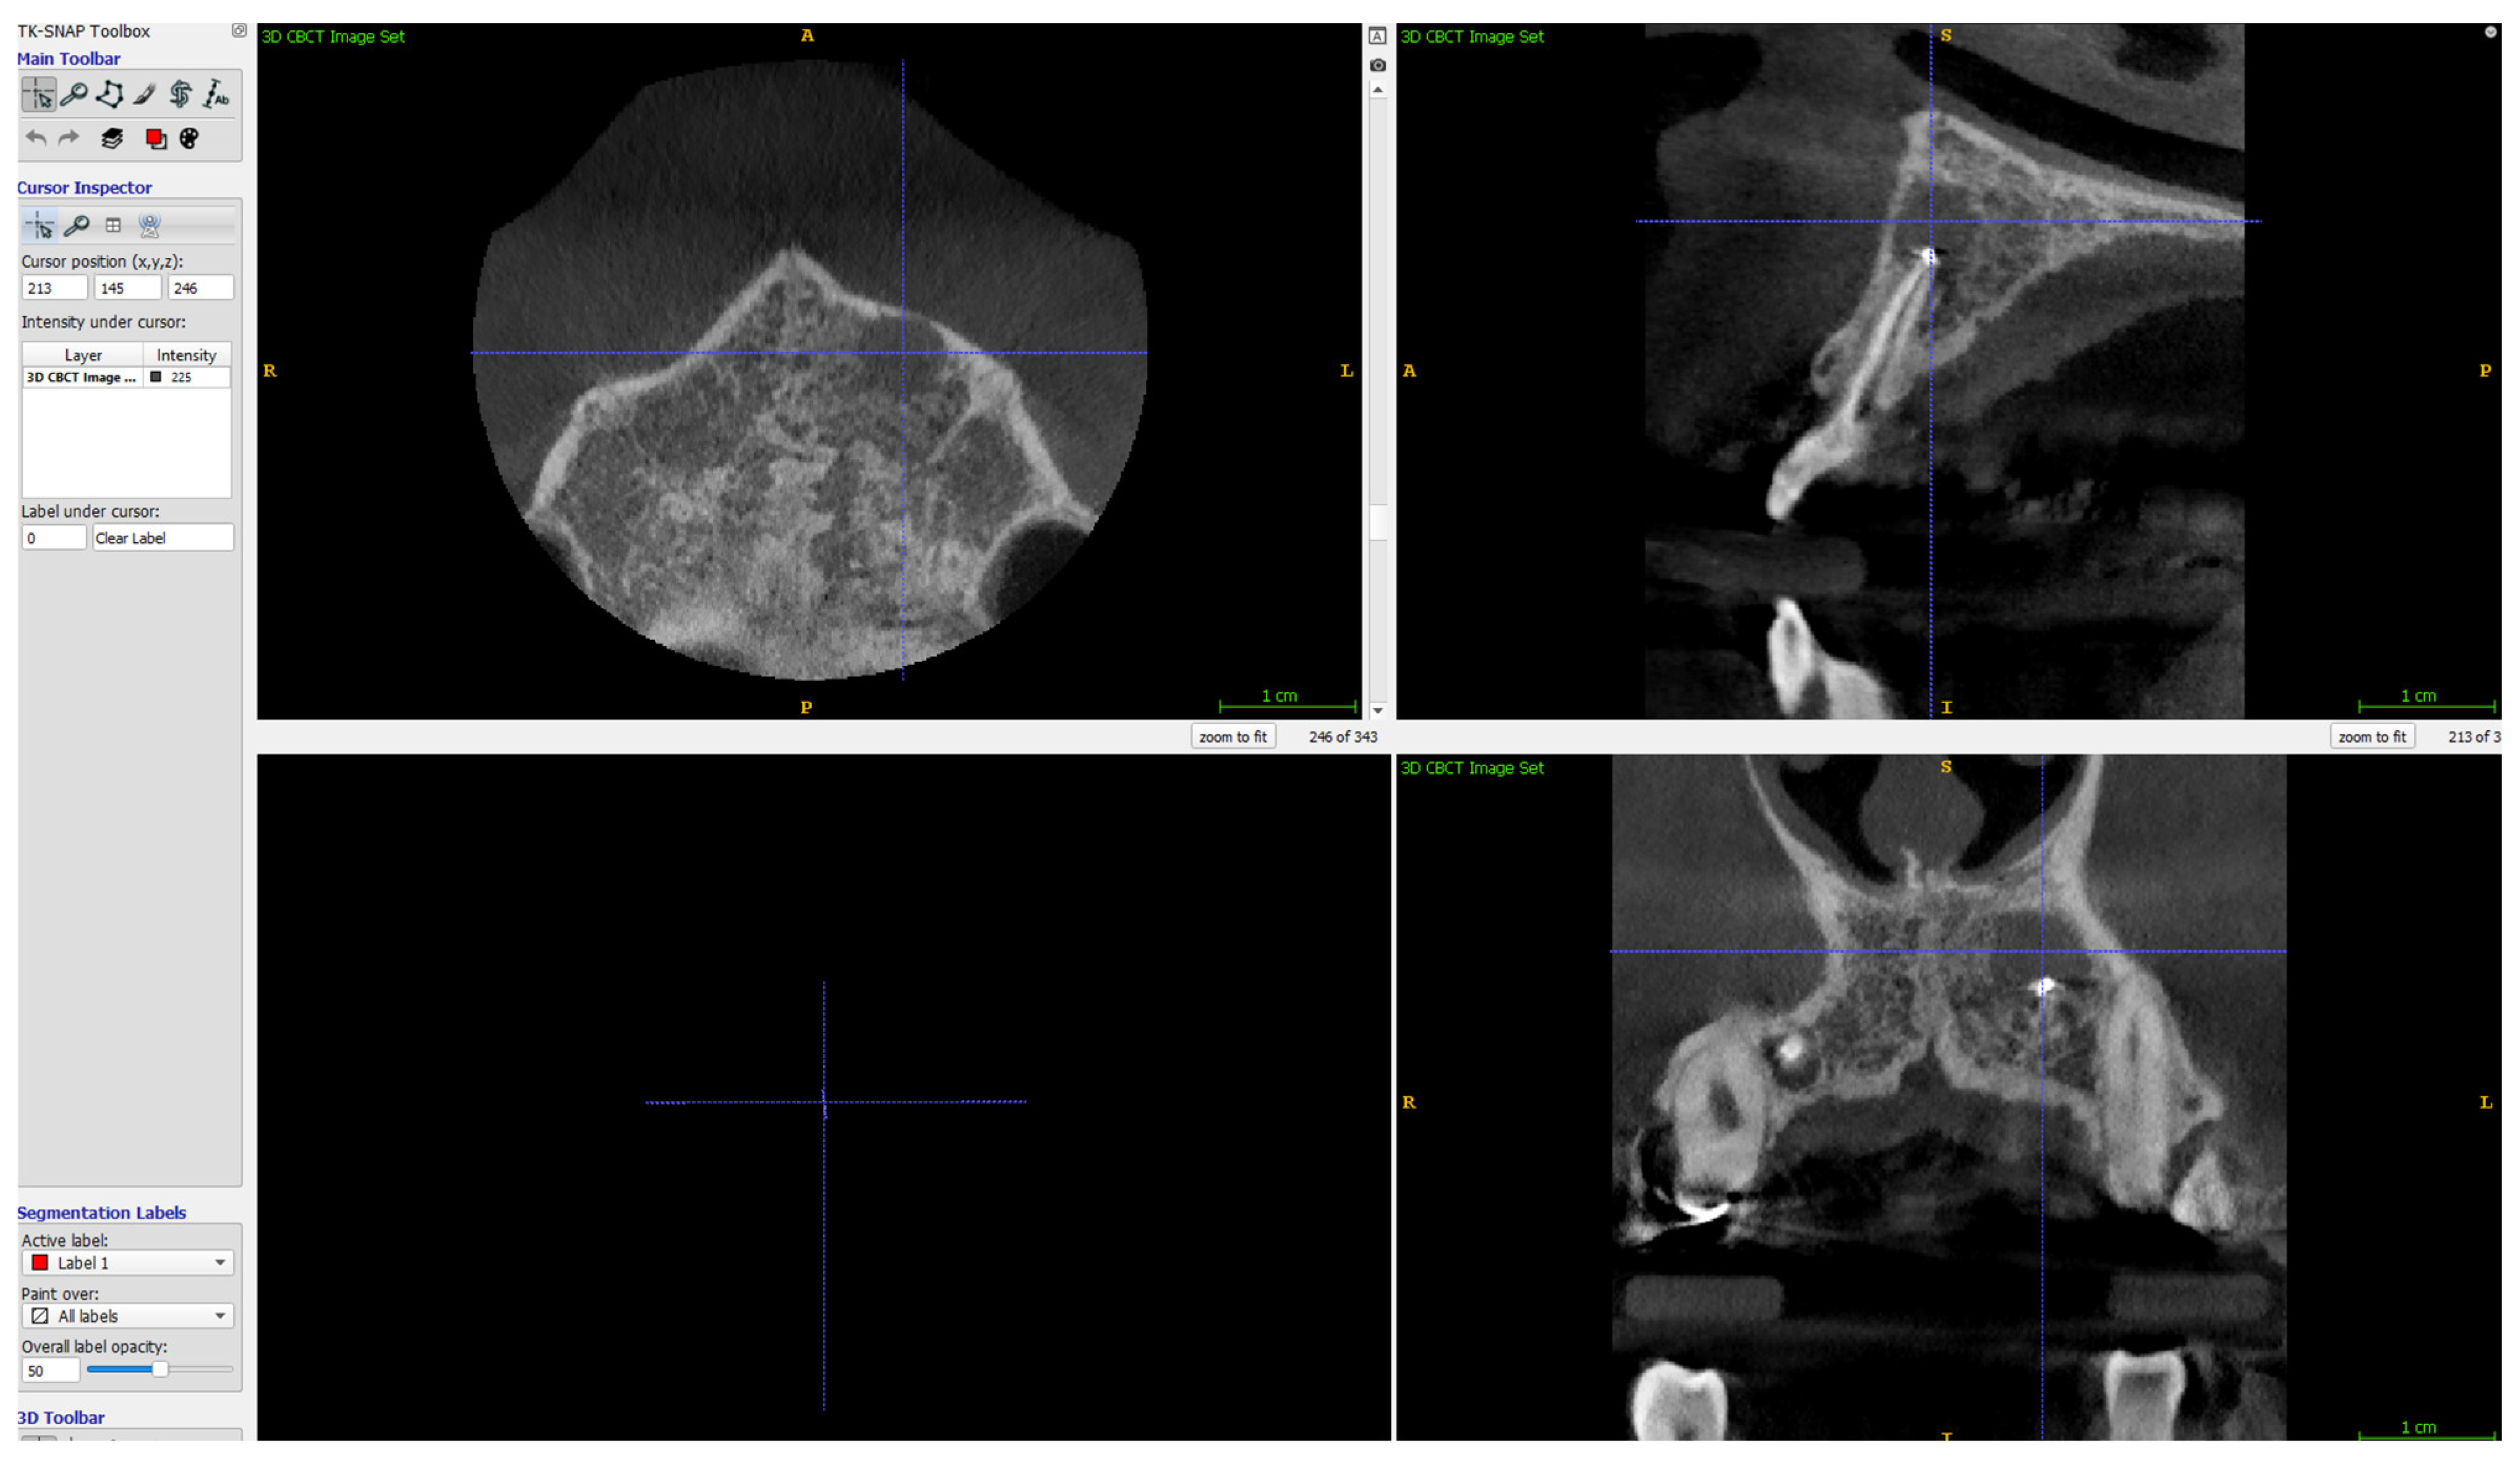

- Apicocoronal maximum diameter (measured in the sagittal section) (Figure 2);

- Buccolingual maximum diameter (measured in the sagittal section) (Figure 3);

- Mesiodistal maximum diameter (measured in horizontal section) (Figure 4);